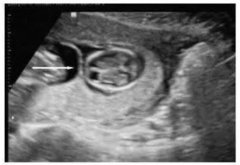

高危胎兒診治技術(shù)_雙胎妊娠超聲檢查技術(shù)規(guī)范

雙胎超聲檢查量亦呈上升趨勢, 據(jù)該項目組中具有代表性的中國醫(yī)科大學(xué)附屬盛京醫(yī)院統(tǒng)計: 2016年雙胎超聲檢查人次數(shù)(5235人次)是2013年 (1917人次)...